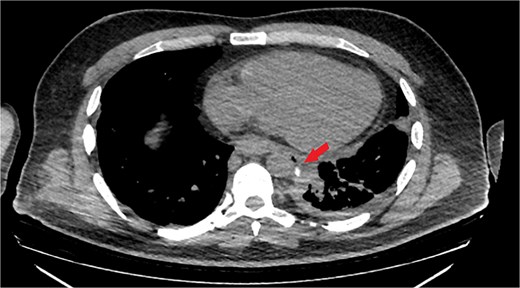

The patient was diagnosed with EP. Gastroscopy showed a 2 cm tear at 27–28 cm from the incisors and erosive esophagitis at the gastroesophageal junction (GEJ). Chest CT confirmed pneumomediastinum, subcutaneous emphysema, pleural effusion, and aspiration pneumonia (Fig. 2). The patient was transferred to the SICU for intensive monitoring. On Day 2, a right thoracotomy was performed, revealing a linear esophageal tear, food collection (mainly red meat), and a 1 cm through-and-through perforation. The procedure included debridement, defect repair with pleural patch reinforcement, and chest tube placement. The patient was monitored postoperatively in the SICU. On Day 4, the patient was extubated, and gastroscopy on Day 10 confirmed healing. An esophageal stent was placed on Day 11, with gradual clinical improvement and tolerance of oral fluids. Chest tubes were transitioned to water-seal drainage. Recurrent stent migrations occurred on Days 15, 17, and 19, requiring repositioning and eventual removal. On Day 20, bronchoscopy identified a broncho-esophageal fistula, and chest CT showed reduced leakage (Fig. 3). The patient was kept nothing by mouth (NPO) for further healing.

Chest CT scan with oral contrast showing significant reduction in the amount of leaked contrast (small rim remaining) with mild decrease in the amount of left pleural effusion and associated collapse consolidation as well as pneumomediastinum.